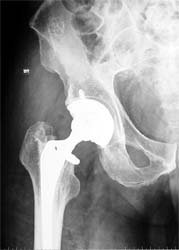

骨性关节炎关节软骨破坏,股骨头坏死 股骨颈骨折,容易发生不愈合

切除病变的股骨头,全髋置换